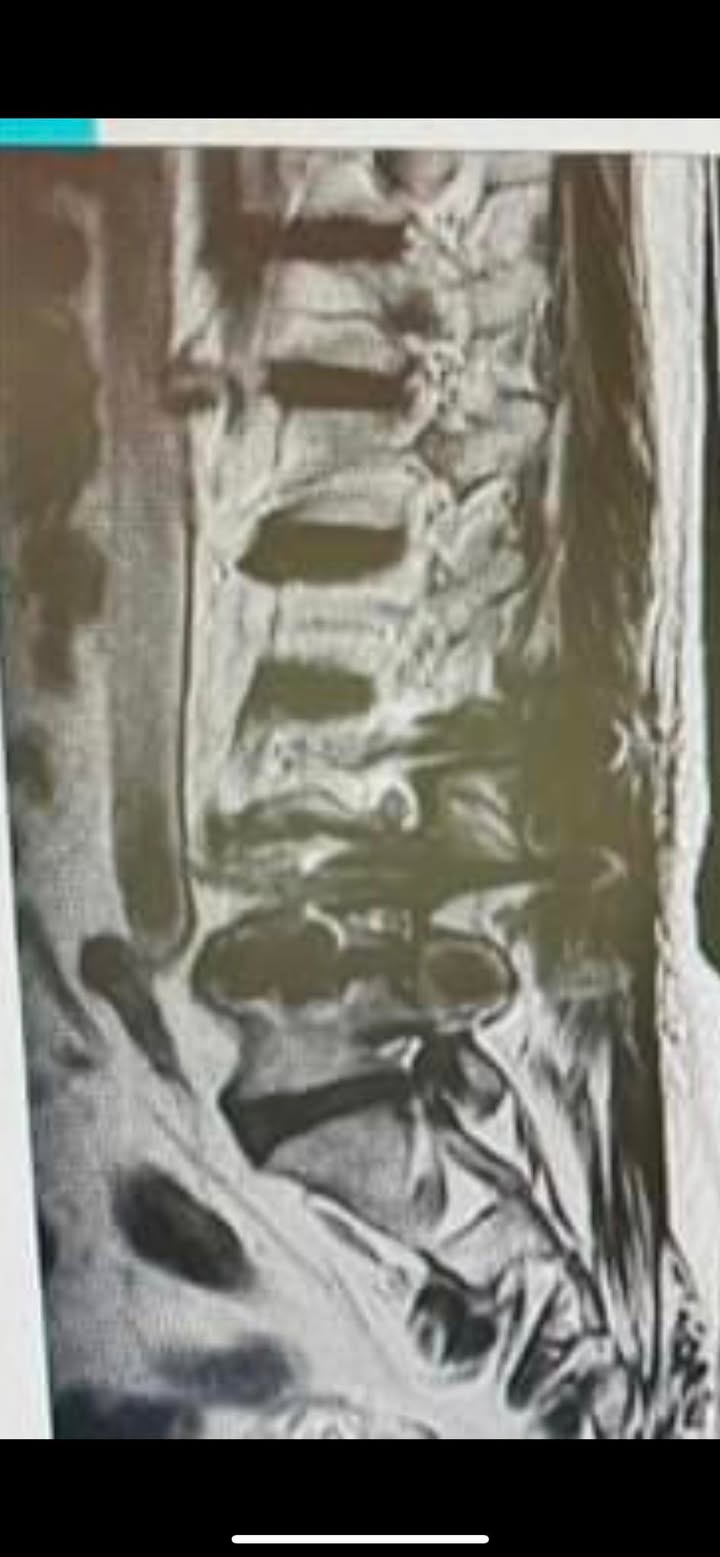

Cervical Spine Treatment Cases 腰椎治療案例 坐骨神經痛痛到站不起來!保守治療六週內逆轉巨大腰椎脫垂 2022.07.03 罕見椎弓解離合併椎體滑脫案例:脊椎整合中醫成功避開手術之路 2022.06.09 #脊椎手術開完刀就一定皆大歡喜嗎 #三分鐘瞭解脊椎手術失敗疼痛症候群 #為什麼如此尖... 2022.06.10 #腿部疼痛或抽筋當心脊椎管狹窄症 #五大症狀自我檢測怎麼做 #腿麻走不動之脊椎狹窄... 2022.06.09 開了三個多小時的車只為了與你相遇。 如果不是有強大的效果跟正能量如何支撐 患者從南... 2022.05.27 #椎間盤突出醫案記實 #向前彎腰極度疼痛導致工作品質下降 #生活上無法自行穿襪子一彎... 2022.05.24 #椎間盤突出醫案紀實 #長時間腰椎痠痛嚴重影響了生活品質 #八週的治療完全改善 #... 2022.05.17 #腰椎滑脫會有什麼症狀 #患者疼到任何姿勢都痛止痛藥也無效 #十二次的密集治療輕鬆... 2022.05.05 #十四次密集治療輕鬆很多又能再去挑戰硬漢嶺啦 #脊椎整合中醫微創筋膜減壓療法逆轉... 2022.05.04 #腰椎間盤巨大突出脫垂 #原本考慮要開刀了 #最後真的逆轉勝 #來診前已經痛到無法走路 ... 2022.04.30 🎊脊椎整合中醫微創療法讓老美也比讚 🇹🇼🇺🇸醫療成功外交就是👍 😭腰椎髓核切除手術... 2022.04.22 #感謝花蓮鄉親張伯伯熱情見證 #千里迢迢從花蓮台北往返治療11次 #椎管狹窄到底是什們... 2022.04.27 ⭕️腳麻腳冷腰臀疼痛,當心脊椎管狹窄症 🛑五大症狀自我檢測 ❗️腿麻走不動之脊椎狹窄一... 2022.04.06 #腰椎滑脫合併椎管狹窄醫案 #原本痛到無法走路跟坐車 #脊椎整合中醫微創逆轉勝 #治療... 2022.04.02 ➡️腰椎開過三次刀心酸血淚史醫案 🔄什麼時候要考慮打釘子跟置放椎間盤 🟢什麼是下背手... 2022.03.25 ← 上一頁 3 4 5 6 7 下一頁 →